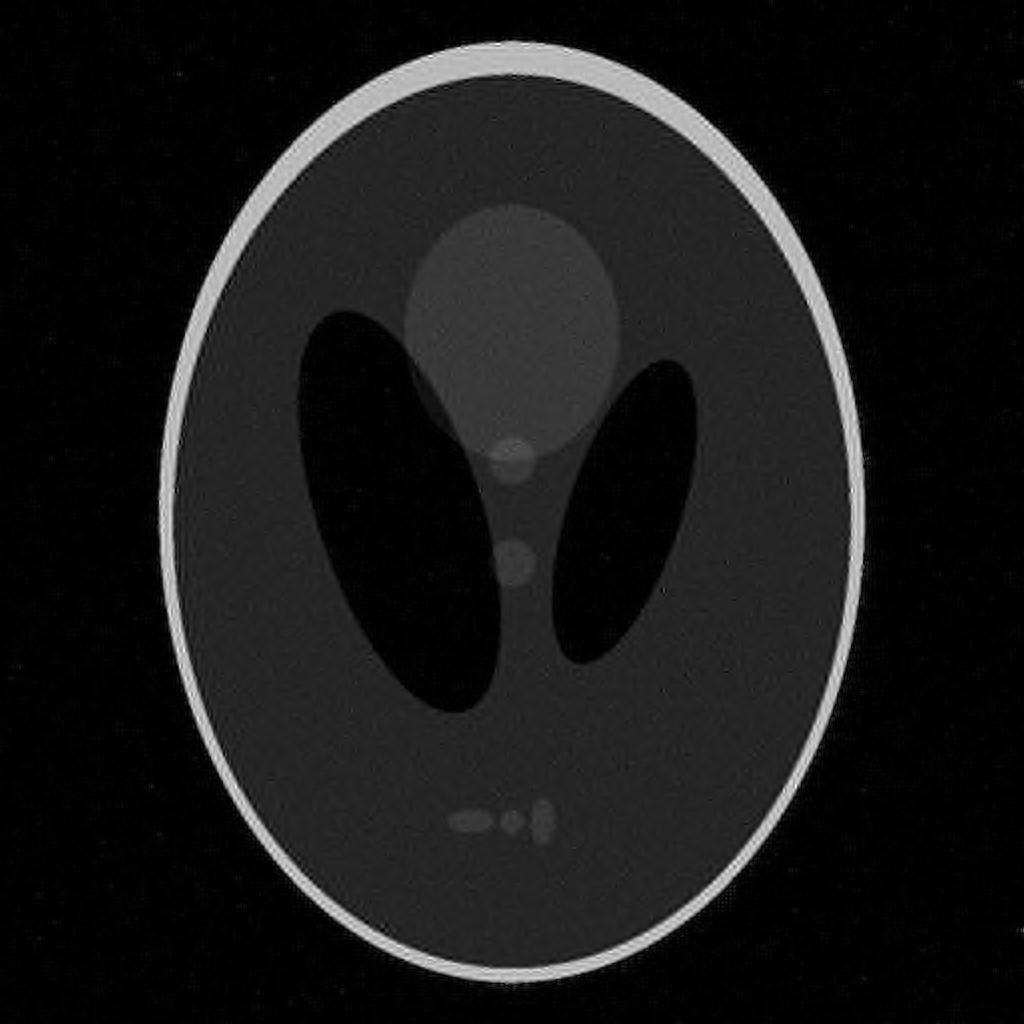

The second imaging application is concerned with medical imaging. Following the ideas from [32, 34], we simulate a multi-channel MRI sensing set-up, first using the same sine waves as in the previous experiment (results displayed in Fig 10), and then using spherical beam pattern (see in Fig. 11 for the results). We generate the classical Shep-Logan phantom, and set its dimension to .

The first experiment, depicted in Fig. 10 shows the results obtained by our method when using a Daubechies 4 sparsifying dictionary. Our results are compared to the single sensor analysis, and the results obtained by the Sum-of-Squares recovery [34, 32].

The recovery is obtained from noisy measurements, in which some additive Gaussian noise with variance has been added. The measurements are obtained by subsampling ( samples) of the Fourier transform. We see here that the fused compressed sensing is better capable of handling a multi-channel problem with unusual illumination (compared to the Sum-of-Squares method). Moreover, more details are preserved, when compared to the single sensor analysis method.

Some noise still appears in the image, but can easily be thresholded further if needed. One important aspect of MR Images that hasn’t been considered in this research, is the fact that they are sparse in gradient. One usually prefers to minimize the Total Variation instead of the norm or another frame using analysis.

Although we have not explicitly written the theory here, the recovered images in Fig. 11 show the results when using a TV minimization instead of the analysis.

| analysis | Sum of Square fusion | Fused analysis | |

|---|---|---|---|

| SSIM | |||

| PSNR | |||

| error |

The results were obtained from a spherical beam illuminating the input image. The measurements are obtained by sampling ( samples) of the Fourier coefficients at random iid from a Gaussian distribution. Again, some Gaussian noise with variance is added to every measurements.

| analysis | Sum of Square fusion | Fused analysis | Fused total variation | |

|---|---|---|---|---|

| SSIM | ||||

| PSNR | ||||

| error |